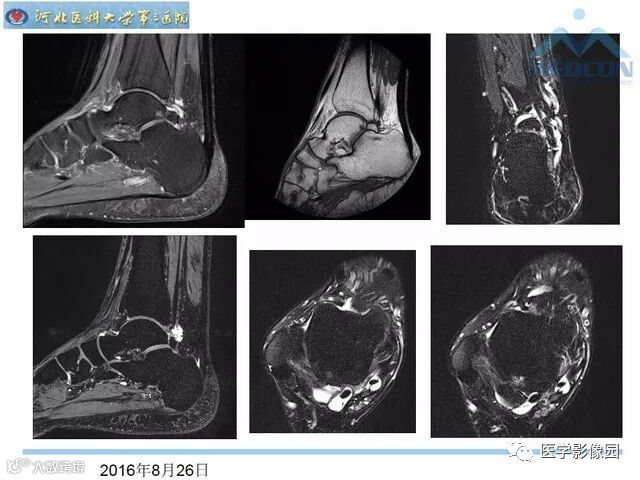

踝关节撞击综合征影像诊断,干货满满,值得收藏!

导读:踝关节撞击综合征影像诊断。干货满满,值得收藏!

踝关节撞击综合征影像诊断。干货满满,值得收藏!